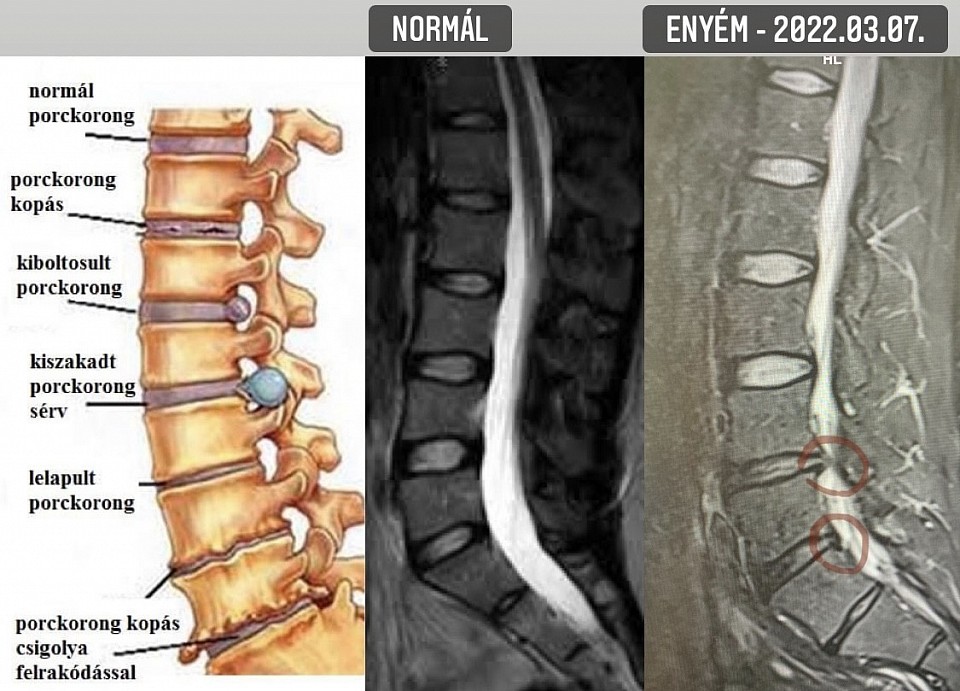

Arra már nem igazán emlékszem hogyan jutottam el otthonról a székesfehérvári MR vizsgálatra. Jó, kocsival. Oké, még vezettem is. De egy örökkévalóság volt valahogy behajtogatni magam a vezetőülésbe, Buksi szerencsére segített. Egész gyorsan megjött a vizsgálat után az orvosi vélemény. Már első blikkre láttam, hogy ehhez kevés lesz a kéttucatnyi szóból álló latin nyelvtudásom. Google, pötyögjük be. Menni fog ez. Különben is, az első mondatból a lumbalis szót még fordítás nélkül is értem. Persze úgy könnyű, hogy magyarul is ugyanúgy van. De a rohadt fájdalom mellé kell egy kis sikerélmény. Tehát gerincferdülés, meszesedés, porckorongsorvadás, eddig semmi komoly, de a harmadik mondat „adja magát”, fordítani sem kell: „Hernia disci intervertebralis foraminalis LIV-V I.s., bal L4 gyöki compresszióval, tünetképző, idegsebészeti konzílium javasolt”. Aha, orvosi szaknyelven tehát a tünetképző jelenti azt, hogy beszarsz a fájdalomtól. „17x10 mm-es extrusio látható, a bal L4 gyököt comprimálja.” Hogy dögölne meg, miért pont engem komprimál?

A hab a tortán, hogy a négyes-ötös csigolya közötti kiszakadt sérv alatt van egy „előboltosult” rész is. Szuper, legalább lesz, ami pár év múlva majd ki tud szakadni. Éljen a húszévnyi ülőmunka!